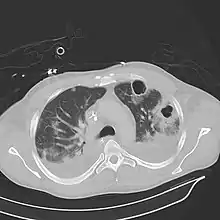

Pulmonary abscess on CT scan

Lung abscesses are often on one side and single involving posterior segments of the upper lobes and the apical segments of the lower lobes as these areas are gravity dependent when lying down. Presence of air-fluid levels implies rupture into the bronchial tree or rarely growth of gas forming organism.